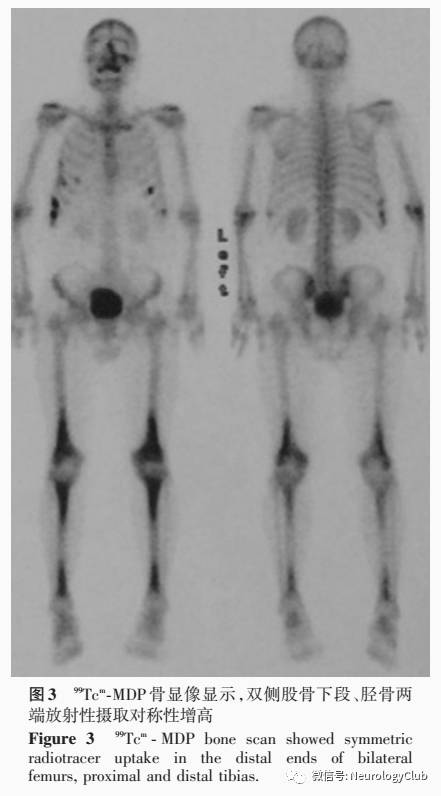

辅助检查  实验室检查:血尿便常规、肝肾功能试验、凝血功能试验均于正常值范围。血清脂质甘油三酯(TG)为3.92mmol/L(0.45-1.70mmol/L),余项于正常值范围。血清超敏C-反应蛋白(hsCRP)5.36mg/L(0-3mg/L),红细胞沉降率(ESR)24mm/h(0-15mm/h),抗核抗体(ANA)谱、抗中性粒细胞胞质抗体(ANCA)、抗可提取性核抗原(ENA)抗体和水通道蛋白4(AQP4)抗体和血管紧张素转换酶(ACE)均呈阴性;CD8+T细胞异常激活。血清TORCH10项中巨细胞病毒IgG和IgM阳性、I型和II型单纯疱疹病毒IgG阳性,余均呈阴性,巨细胞病毒DNA和pp65抗原阴性;结核分枝杆菌抗体、结核杆菌感染T细胞斑点试验(T-SPOT.TB)、布氏杆菌凝集试验、莱姆病毒抗体、1,3-β-D葡聚糖检测(G试验)、隐球菌抗原、人类免疫缺陷病毒(HIV)抗体、梅毒螺旋体明胶凝集试验(TPPA)均呈阴性。空腹血糖水平6.60mmol/L、糖化血红蛋白(HbA1c)正常;内分泌激素检测促肾上腺皮质激素(ACTH)12.12pmol/L(0-10pmol/L),皮质醇、生长激素(GH)、胰岛素样生长因子1(IGF-1)等均于正常值范围;性腺激素检测睾酮5.86nmol/L(6.07-27.27nmol/L),卵泡刺激素(FSH)、黄体生成素(LH)、泌乳素(PRL)、雌二醇、孕激素均于正常水平。血清肿瘤标志物筛查未见明显异常,血清抗Hu、Yo、Ri抗体阴性。腰椎穿刺脑脊液压力135mmH2O,白细胞计数2×106/L,蛋白定量0.67g/L、葡萄糖4.20mmol/L、氯化物123mmol/L,细胞学涂片白细胞为10/0.50ml,乳酸2.47mmol/L(1.00-2.80mmol/L);TORCH10项、EB病毒和巨细胞病毒DNA、快速血浆反应素试验(RPR)、细菌和真菌涂片、奴卡菌涂片、墨汁染色、隐球菌抗原均呈阴性;甲胎蛋白(AFP)、癌胚抗原(CEA)阴性;寡克隆区带、AQP4抗体阴性;脑脊液囊虫IgG抗体阴性。复查PET显示,右侧小脑蚓部旁、脑桥背侧偏左、右侧额叶半卵圆中心代谢增高(SUVmax=12.10,图2),可疑恶性病变,建议行进一步检查;右侧小脑弥漫性代谢降低,考虑继发性改变;双侧上颌窦炎,右侧上颌窦囊肿。复查MRI(2015年2月)显示,垂体后叶高信号消失,增强后丘脑和垂体柄明显增粗并强化(图1);左侧颞叶、右侧顶叶病灶基本同前,小脑、脑干病灶较前增大。胸部高分辨力CT检查可见右肺下叶有结节形成;右肺上叶、左肺下叶少量斑片状和索条状高密度影;左侧胸膜局部增厚。99Tcm-亚甲基二膦酸盐(99Tcm-MDP)骨显像显示,双侧股骨下段、胫骨两端放射性摄取对称性增高,拟诊为非朗格汉斯细胞组织细胞增生症中的Erdheim-Chester病;左侧上颌骨、右侧第5~9前肋、左侧第6和9前肋放射性摄取增高,考虑骨折(图3);余未见异常。下肢长骨X线显示,双侧胫骨下段骨密度异常。超声心动图未见明显异常。副鼻窦CT显示,右侧上颌窦黏膜下囊肿;双侧上颌窦和筛窦炎;左侧中鼻道狭窄。

神经科主治医师  患者为中年男性,隐匿发病,呈慢性病程。临床主要表现为:(1)多饮、多尿、烦渴,口服醋酸去氨加压素治疗后症状得到控制。(2)近1年出现行走不稳、构音障碍,但病情进展相对缓慢,大剂量甲泼尼龙冲击治疗和泼尼松口服治疗效果欠佳,临床症状和影像学改善均不明显。(3)双侧上眼睑和右侧背部新发黄色结节。定位诊断:(1)行走不稳,构音障碍,右侧指鼻试验和跟-膝-胫试验欠稳准,意向性震颤,反击征阳性,水平眼震,定位于小脑及其联系纤维,以右侧显著。(2)双侧闭目有力,右侧鼻唇沟浅,口角低,考虑右侧中枢性面瘫,定位于面神经核以上的左侧皮质脑干束;右侧肱二头肌反射、膝腱反射略高于左侧,右侧Babinski征可疑阳性,定位于左侧皮质脊髓束。结合影像学,上述症状与体征可以用脑干和小脑病变解释。(3)多饮、多尿、烦渴,MRI显示下丘脑和垂体柄增粗并强化,提示下丘脑-垂体系统受累。(4)新发皮肤结节,存在皮肤受累。(5)无骨痛主诉,但99Tcm-MDP骨显像和下肢长骨X线提示长骨受累,为骨质硬化表现,非破坏性改变。定性诊断:患者中年男性,发病隐匿,慢性病程,无发热、头痛、恶心、呕吐等症状;影像学表现为颅内幕上和幕下多发病灶,以脑干和小脑显著,MRI呈长T1、长T2信号,周围脑组织水肿,增强扫描呈结节状强化,PET显示病灶呈高代谢。提示影像学表现较重而临床症状较轻,病情进展相对缓慢,同时有下丘脑-垂体系统、皮肤和骨骼受累,应考虑肿瘤或系统性病变。(1)肿瘤:患者脑组织活检未见明确肿瘤证据,仅个别神经胶质细胞异型性,但18F-FDGPET显示多发性高代谢病灶,故不能排除肿瘤可能。脑组织活检结果阴性不排除与取材部位不准确有关,但病程较长、进展相对缓慢不支持肿瘤诊断。(2)系统性疾病:除脑实质内多发性病变外,尚有下丘脑-垂体系统、皮肤和骨骼受累,故应考虑系统性疾病。肉芽肿性多血管炎(又称韦格纳肉芽肿)和结节病可累及皮肤和中枢神经系统,以硬脑膜常见,也可累及鞍区和脑实质,但该例患者未见肺部病变、激素治疗无效、血清ANCA和ACE呈阴性,诊断证据不足。鞍区和颅内多发性病变的鉴别诊断还应考虑组织细胞增生性病变,除中枢神经系统病变外,此类病变也可累及多个系统,但仅根据临床表现和影像学鉴别诊断困难,需以组织活检术和特殊染色为诊断依据。该例患者皮肤组织活检CD68阳性,S-100可疑阳性,CD1a和CD207阴性,结合多系统受累表现,考虑非朗格汉斯细胞组织细胞增生症中的Erdheim-Chester病。鉴别诊断:(1)炎性脱髓鞘病变。脑组织活检提示髓鞘脱失性炎症反应,应考虑中枢神经系统炎性脱髓鞘疾病。但该例患者颅内病灶分散,颞叶和顶叶并非典型的脱髓鞘病变部位,而且存在脑实质病变1年余,病灶仍明显强化伴周围组织水肿,糖皮质激素冲击治疗后临床症状和影像学表现无改善,均不支持诊断。(2)感染。该例患者在病程中无发热、头痛症状,脑脊液蛋白定量稍高,呈轻度淋巴细胞反应,脑实质多发病灶,并非常见细菌、寄生虫感染,需谨慎排除特殊类型病原菌,经完善脑脊液细菌、真菌、病毒、寄生虫等筛查项目,均未见明确的感染证据。

Erdheim-Chester病临床表现多样,可累及多器官,与组织细胞增生性病变的其他类型,如朗格汉斯细胞组织细胞增生症、Rosai-Dorfman病(RDD)等鉴别诊断困难(1)骨骼骨骼受累较常见,主要累及四肢长骨,表现为对称性骨质硬化,所有患者均可见长骨受累,但仅50%患者有骨痛表现朗格汉斯细胞组织细胞增生症则主要累及颅骨、四肢近端骨、骨盆和肩胛骨。Erdheim-Chester病放射性核素骨显像表现为长骨干骺端对称性放射性核素聚集,X线呈现骨主干和干骺端骨质硬化。(2)中枢神经系统有25%-50%的患者存在中枢神经系统病变,可累及脑实质和脑膜脑实质病变见于脑桥、齿状核和大脑半球,MRI以病灶强化征象为主,临床应注意与原发性肿瘤和继发性转移瘤、脱髓鞘病变和炎症相鉴别;而脑膜受累则应注意与脑膜炎、肉芽肿性病变、Rosai⁃Dorfman病相鉴别。中枢神经系统受累提示预后不良,是死亡结局的独立危险因素,故应行基线MRI评价。(3)皮肤常见皮肤损害为眼睑黄斑瘤,面部、颈部、躯干、腹股沟和腋窝也可见黄色或棕红色斑块但仅从皮肤损害形态难以与幼年性黄色肉芽肿(JXG)相鉴别,后者鲜有多系统受累病例(4)内分泌系统约25%的患者有尿崩症表现,以及高泌乳素血症、促性腺激素缺乏、血清睾酮降低等内分泌功能异常影像学检查可见腺垂体、垂体柄、下丘脑受累,部分患者虽有上述结构受累但并无内分泌功能异常的临床表现。(5)肺部逾50%的患者肺部受累,病变主要位于肺实质和胸膜但可不出现临床症状,仅少数病例表现有咳嗽或呼吸困难。高分辨力CT显示肺叶间隔增厚、肺组织“毛玻璃”样改变,但单纯肺实质病变不常见。(6)眼部:约25%的患者出现单眼或双眼浸润性病变,眶内占位表现为突眼,严重者可有眼肌麻痹或视力下降,应注意与炎性假瘤、Graves病、肉芽肿性病变、淋巴瘤等相鉴别(7)心血管系统心血管系统受累较为常见但多无临床症状,约2/3的患者累及胸主动脉或腹主动脉,形成典型的“coated aorta”影像学改变;肾动脉受累可以出现肾性高血压心脏病变包括右心房假瘤样病变(pseudo-tumor)、心包纤维化、心脏瓣膜浸润,心脏受累是重要死亡原因(8)腹膜后浸润:约30%的患者影像学检查可见腹膜后浸润,肾脏周围受累可见典型的“hairy kidney”征象,也可引起肾盂积水、输尿管狭窄。腹膜后浸润与腹膜后纤维化不同,一般盆腔、输尿管和下腔静脉不受累。

Erdheim-Chester病的诊断主要依据特征性的组织病理学、临床和影像学表现。(1)组织病理学泡沫细胞(foamy cell)或富含脂质的组织细胞(lipid-ladenhistiocytes)浸润,可见Tonton巨细胞,病灶周围组织纤维化免疫组织化学染色显示CD68、CD163、凝血因子XIIIa阳性,CD1a和Langerin阴性,S-100阴性或弱阳性(2)影像学主要呈现下肢长骨骨干和干骺端对称性骨质硬化,99Tcm-MDP骨显像可见长骨远端放射性高摄取,X线显示骨质硬化PET的敏感性低于放射性骨显像,但可发现骨骼以外的其他器官受累情况,是评价Erdheim-Chester病疾病负荷的重要方法。CT和MRI也可发现骨骼受累,但X线检查易漏诊。此外,CT所示肾脏周围脂肪浸润形成的“hairy kidney”也具有诊断特异性值得注意的是,即使临床和影像学表现典型者,仍需行组织活检术和BRAF基因检测,以明确诊断。Haroche等研究发现,54.17%(13/24)的Erdheim-Chester病患者存在BRAF V600E基因突变;Cangi等改进检测方法,采用锁核酸聚合酶链反应联合焦磷酸测序技术,发现所有Erdheim-Chester病患者(18/18)均存在BRAFV600E基因突变。